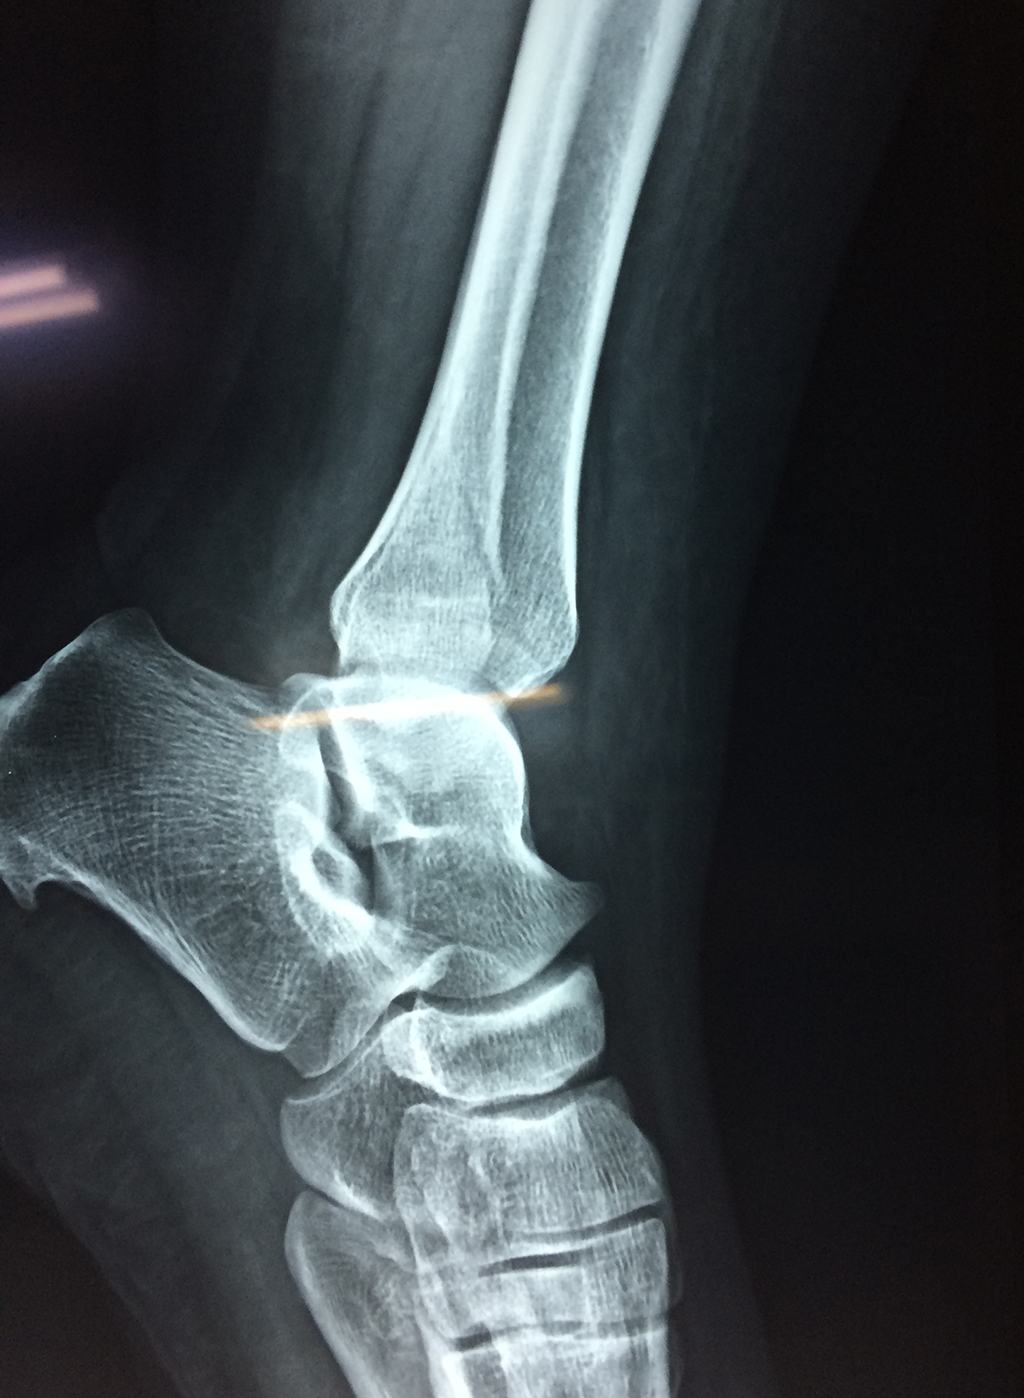

Una fractura de tobillo es la rotura de uno o más de los huesos del tobillo. Estas fracturas pueden ser:

- La fractura se extiende hasta la articulación del tobillo (fractura intra-articular).

- Los tendones o ligamentos (tejidos que sujetan los músculos y los huesos entre sí) están rotos.